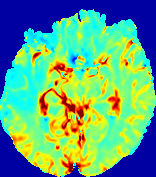

LesionRefer to captionRefer to captionRefer to captionRefer to captionRefer to captionRefer to caption𝐕rgbsubscript𝐕𝑟𝑔𝑏{\bf{V}}_{rgb}Refer to captionRefer to captionRefer to captionRefer to captionRefer to captionRefer to caption𝐕2subscriptnorm𝐕2{\|\bf{V}}\|_{2}Refer to captionRefer to captionRefer to captionRefer to captionRefer to captionRefer to captionRefer to caption3.53.53.52.82.82.82.12.12.11.41.41.40.70.70.70.00.00.0(mm/s)𝑚𝑚𝑠(mm/s)D𝐷DRefer to captionRefer to captionRefer to captionRefer to captionRefer to captionRefer to captionRefer to caption0.0200.0200.0200.0160.0160.0160.0120.0120.0120.0080.0080.0080.0040.0040.0040.0000.0000.000(mm2/s)𝑚superscript𝑚2𝑠(mm^{2}/s)Slice #1Slice #2Slice #3Slice #4Slice #5Slice #6

Figure 3: PIANO feature maps for one stroke patient, where the lesion is located in the left hemisphere. Top row: segmented stroke lesion region (white) on different slices, obtained from ISLES 2017. The corresponding slices for the PIANO feature maps are shown in the following rows.

For a better insight into an estimated velocity field 𝐕𝐕{\bf{V}} and diffusion field 𝐃𝐃{\bf{D}}, we compute the following maps: (1) 𝐕rgbsubscript𝐕𝑟𝑔𝑏{\bf{V}}_{rgb}: Color-coded orientation map of 𝐕=(Vx,Vy,Vz)T𝐕superscriptsuperscript𝑉𝑥superscript𝑉𝑦superscript𝑉𝑧𝑇{\bf{V}}=(V^{x},V^{y},V^{z})^{T}, obtained by normalizing 𝐕𝐕{\bf{V}} to unit length and mapping its 3 components to red, green, blue respectively; (2) 𝐕2subscriptnorm𝐕2\|{\bf{V}}\|_{2}: 222 norm of 𝐕𝐕{\bf{V}}; (3) D𝐷D: scalar field in Eq. 5.

Fig. 3 and Fig. 4 show the PIANO feature maps estimated from two ISLES 2017 patients: all are highly consistent with the lesion in both cases. Details of the blood flow trajectories are revealed in 𝐕rgbsubscript𝐕𝑟𝑔𝑏{\bf{V}}_{rgb} by the ridged patterns and the sharp changes of colors in the unaffected (right) hemisphere, while the flat patterns appearing within the lesion provide little directional information about the velocity and indicate low velocity magnitudes. Velocity magnitudes are more directly visualized via 𝐕2subscriptnorm𝐕2\|{\bf{V}}\|_{2}, from which one can easily locate the lesion where 𝐕2subscriptnorm𝐕2\|{\bf{V}}\|_{2} is low. D𝐷D also indicates lower diffusion values in the lesion, though with less contrast potentially due to the fact that it captures the accumulated effect of CA diffusion at the voxel-level.